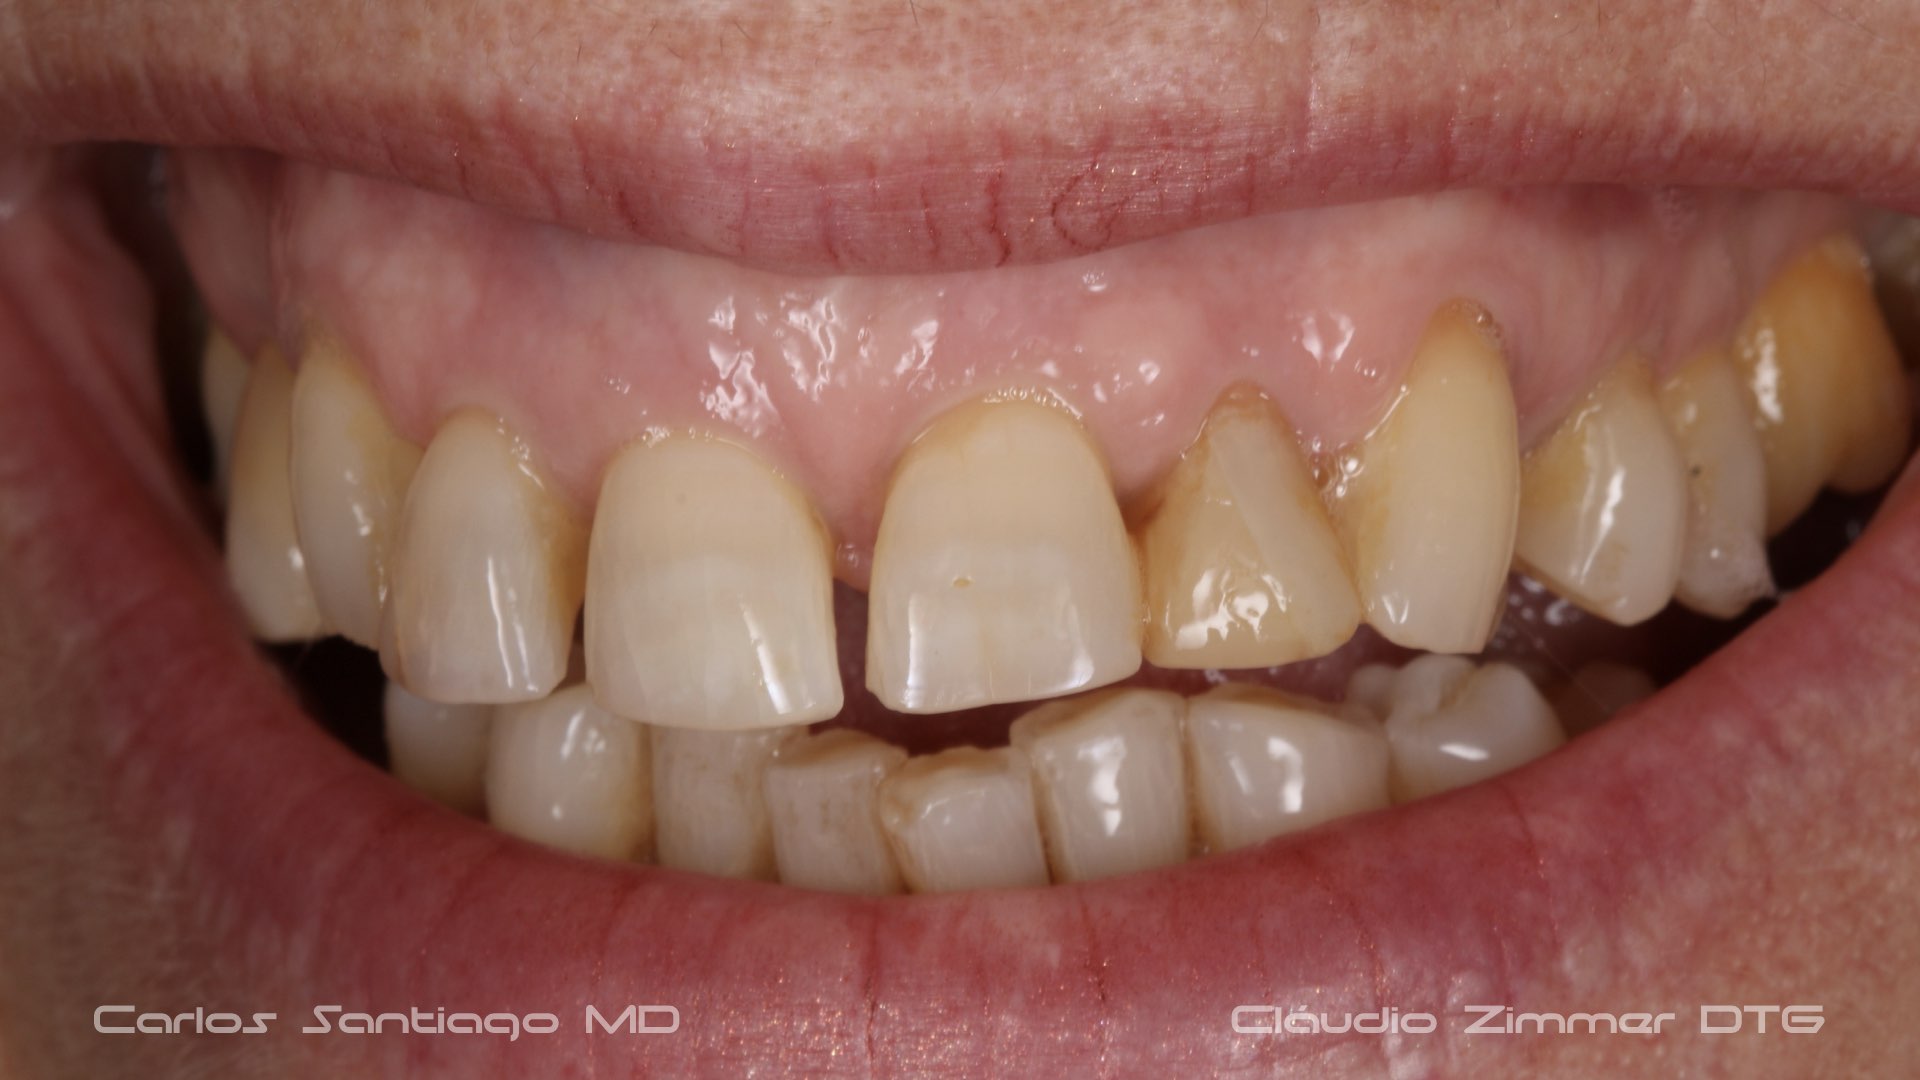

As Facetas Cerâmicas (lentes de contacto dentárias ou laminados), permitem corrigir da maneira mais estética e conservadora possível, problemas de forma e tamanho, côr e posição dos dentes, bem como substituir restaurações antigas e inestéticas.

São aderidas químicamente ao esmalte dentário de uma forma permanente, com o objectivo de melhorar a estética dos nossos pacientes.